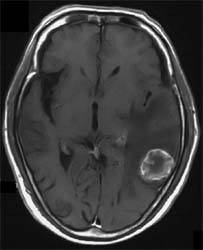

CT、MRIで境界明瞭な腫瘤でいわゆるリング状造影効果をしめすものが多い。